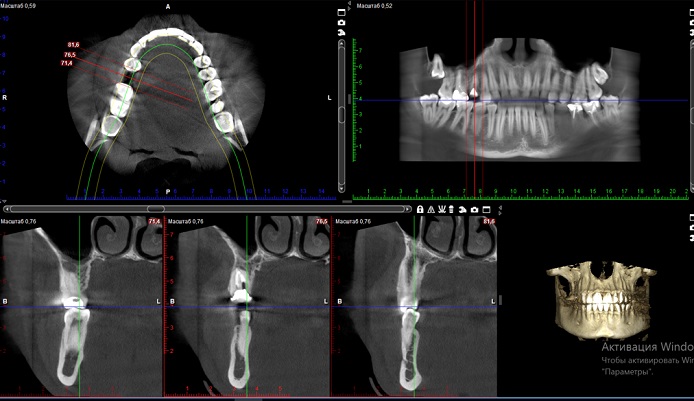

Комп’юторна Томографія: для чого вона і що це взагалі

таке?

томографію (КТ). Це сучасний метод діагностики, який дозволяє дізнатись про

особливості будови щелеп та зубного ряду, та виявити приховані патології

різного роду.

КТ необхідна, щоб:

побачити та оцінити

стан зубів, які ще не прорізалися, анатомію каналів та якість лікування.

Виявити приховані та

вторинні карієси

уточнити глибину

пошкодження

оцінити ступінь

руйнування щелепної кістки.

КТ потрібна для

отримання детальної картини стану зубо-щелепного апарату, постановки точного

діагнозу. Від цього залежить підбір та ефективність лікування.